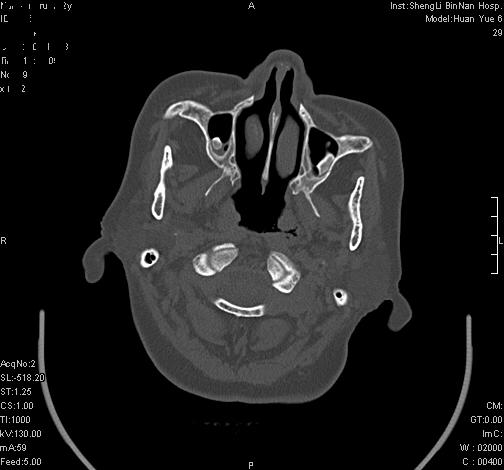

上次发的片子,不够细微。误导了大家,请大家再重新看一下,思路会更清晰。

双上颌窦高密度,其内见水样密度.考虑双上颌窦骨瘤伴上颌窦炎.

双上颌窦高密度,左侧病灶下部与左上颌窦底部骨质相延续,支持双上颌窦骨瘤

双侧上颌窦上部黏膜明显增厚、窦腔缩小,偏后侧窦壁骨质毛糙、模糊,窦腔内见条块状钙化。结合双侧鼻甲黏膜明显增厚,以及临床症状,

考虑:双侧上颌窦霉菌性鼻窦炎

双侧上颌窦密度增高,粘膜增厚,内见条片状钙化,窦壁无增生与破坏征象,双侧鼻甲粘膜肥厚.

意见:双侧霉菌性上颌窦炎.

温习:真菌性鼻旁窦ct特征 1)非侵袭性病变者可涉及到鼻腔和鼻窦,多为单侧,上颌窦最多见.2)ct示窦腔内软组织增生影,可呈息肉状,+c可强化3)增生软组织影内可见散在斑片状或沙砾状钙化区,此为其典型特点,4)

非侵袭性病变可见窦壁骨质增生,破坏少见;侵袭性病变可见窦壁骨质破坏.

支持双测上颌窦霉菌性鼻窦炎。双测少见。

如此好的机器,为何不来点冠状面和失状面重建的图象呢,或许会提供更多的信息供大家参考。